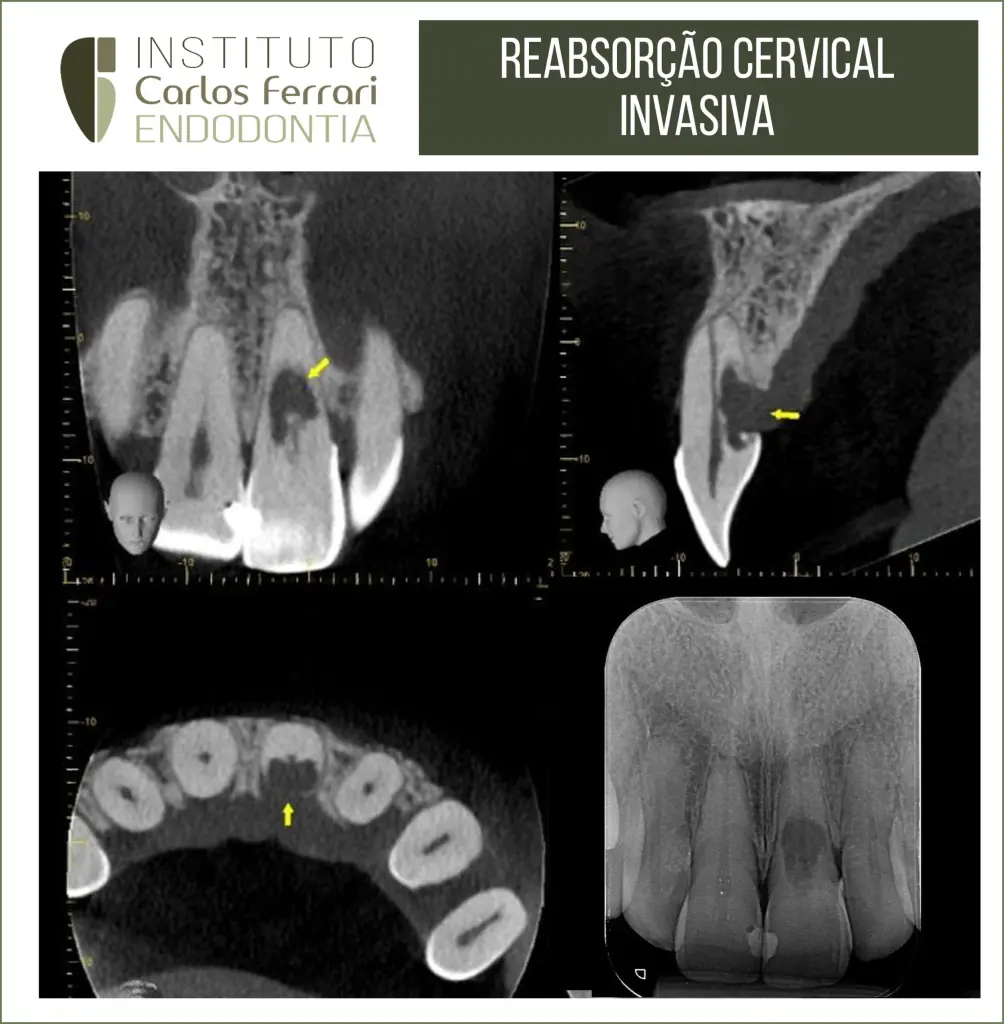

Reabsorção radicular cervical externa. Paciente 30 anos, sexo feminino, com diagnóstico de reabsorção radicular cervical invasiva, após queixa de dor na região gengival palatina. Na primeira sessão foi realizada a descontaminação do espaço endodôntico e medicação com Bio C Temp (Angelus).

Retratamento em dente com reabsorção externa